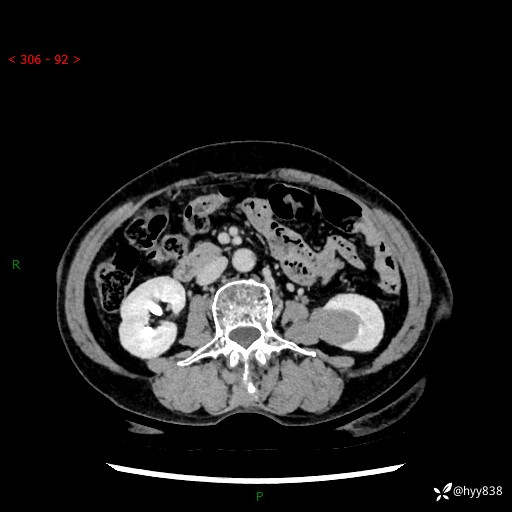

72岁/女,检查发现左肾占位1天。为了满足诊断,常规四期后,又加了延迟期-结果公布~

【患者信息】:72岁/女

【主诉】:检查发现左肾占位1天

【现病史及既往史】:患者于1天前检查发现左肾占位,无畏寒发热,无咳嗽咳痰,无腰腹部疼痛不适,无肉眼血尿、无尿频尿急症状,起病来,患者未行特殊治疗,为求进一步诊治,门诊以"左肾占位"收治入院。 发病来患者精神、饮食、睡眠良好,小便如上,大便正常,体重无明显变化。

【检查】:肾脏CT平扫+增强